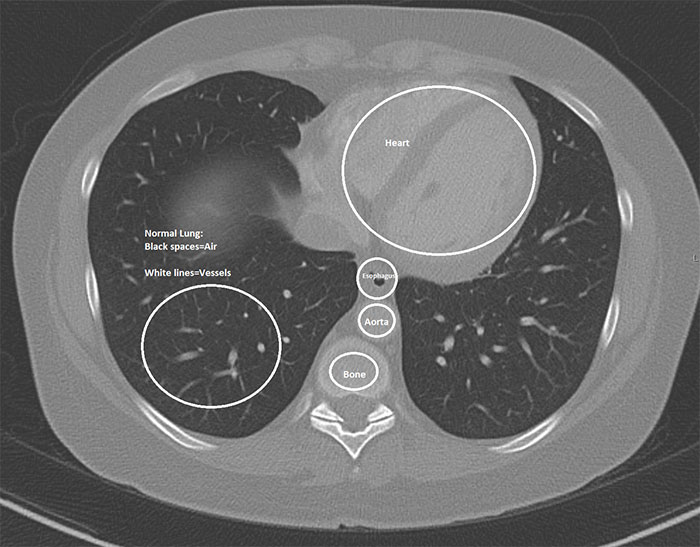

Imgur user and radiologist HeyYoMikey8 said the unknown future is the hardest part of the coronavirus pandemic. HeyYoMikey8 believes it is our own responsibility to educate ourselves so we can all do our part during these difficult times. So, to make it easier for us, the health professional shared what they’re seeing in cases of Covid-19 radiographically. The comprehensive commentary, as well as images used to help in the diagnosis and managing complications or evaluating the progression of the disease, should definitely broaden your understanding of what we’re all facing.

Interestingly, in the early days of the coronavirus outbreak, radiological imaging was not regarded as a way to confirm evidence for COVID-19 cases. Instead, authorities relied on a positive result of the PCR nucleic test. The supply of the PCR test kits, however, was limited and getting back the results took a long time. So, Chinese health authorities soon recognized these difficulties and changed the diagnostic strategy in their 5th edition of the Guidelines on Diagnosis and Treatment of COVID-19. As a result, radiological features of COVID-19 were included as one of the three determinant clinical manifestations to confirm a suspicious patient. The high efficiency, reliability, and accessibility of the radiological diagnostic technology have helped tremendously in identifying the disease. These processes were soon enhanced further by the introduction of artificial intelligence (AI) algorithms.

This could mean CT scanners were to be shut down for up to an hour after a single scan, severely limiting throughput for other patients including for emergent indications like trauma. “The radiology technologists are the real unsung heroes in all of this as they have to deal directly with many potentially infected patients to get their imaging done timely and appropriately, and should be seriously commended right now. We face problems with the diagnosis because a negative study does not rule out the disease, as it may have not yet manifest as an infiltrate despite the infection being present (false-negative scans).”

“Secondly, although certain concerning patterns suggesting COVID-19 on imaging have emerged, all findings are strictly nonspecific and therefore do not entirely rule in the diagnosis, and require additional confirmation as it could still be other entities such as Influenza pneumonia.”

“Finally, all radiology is a business like any other, and we have canceled or deferred almost all elective imaging procedures to help stall the spread of infection and make room for a potential surge of COVID-19 cases,” the radiologist explained. “Therefore, our imaging volumes have dropped by upwards of 50% basically overnight, leaving us with a lack of work for our normal staffing (requiring forced vacations) and a large dip in revenue which jeopardizes our ability to pay the bills and keep our nonphysician employees employed and paid. I do think radiology has helped us at least in this early stage to identify many presumptive cases that were not being considered as COVID-19 at their presentation … It may be helpful for follow up evaluation for potential complications such as ARDS or pleural effusions. Also, there are patients with respiratory symptoms now concerning COVID-19 that have imaging findings/patterns more consistent with other etiology such as bacterial pneumonia or pulmonary embolism, therefore helping to rule out many cases and guiding other appropriate treatment.”